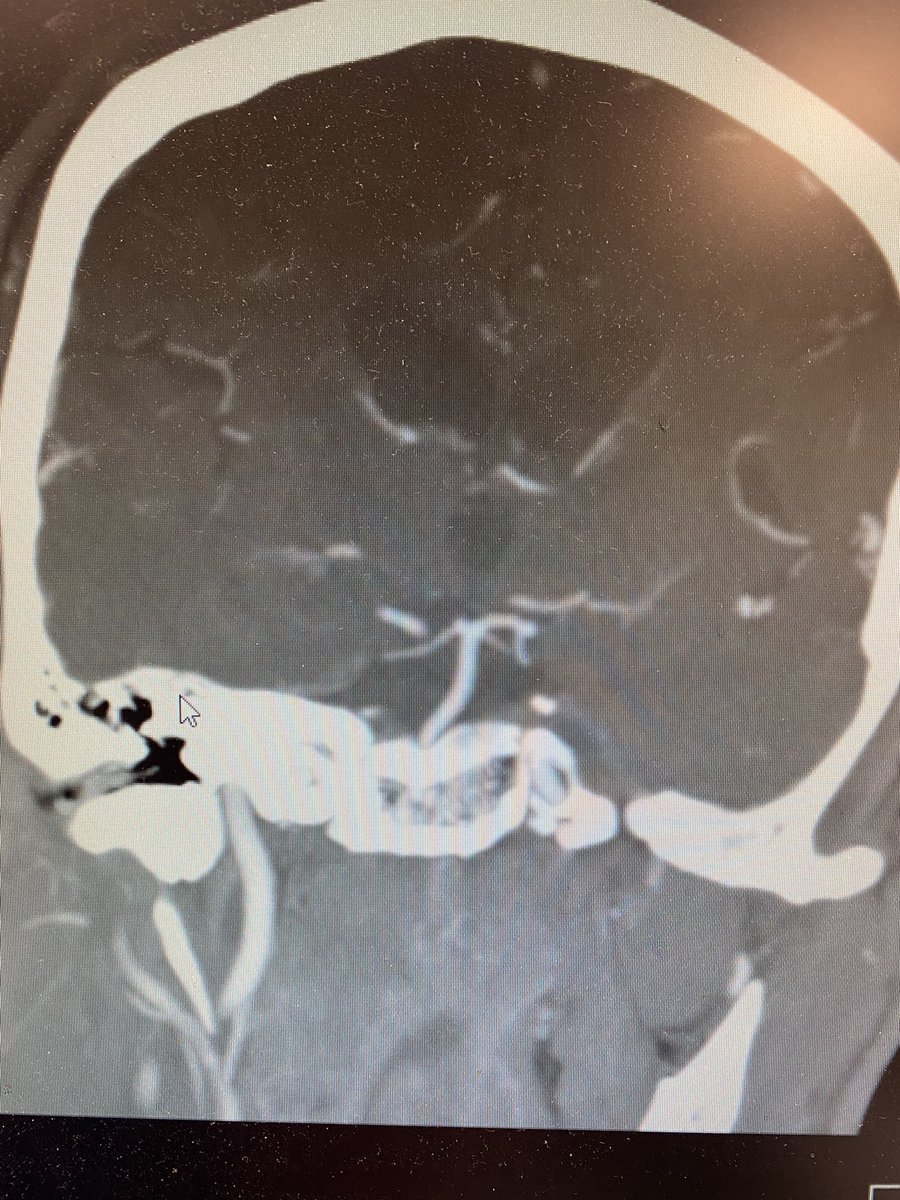

You got it! Artery of Percheron stroke leading to depressed mental status and nuclear IIIrd nerve palsy! Here is a first reference bmcneurol.biomedcentral.com 8/x

Mri also revealed other small embolic strokes and a cardio embolic source is suspected. Search for atrial arrhythmia will continue as an outpatient. 12/x